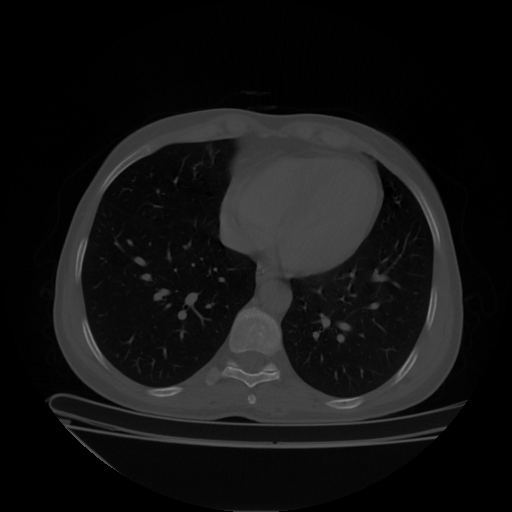

Image Grid

4×3 grid: Rows show different image types (Original NATIVE, Reconstructed NATIVE, Original VENOUS, Generated VENOUS), Columns show windowing techniques (No Window, Lung Window, Mediastinum Window)

Original VENOUS CT scan

No window - Raw intensity values

Original VENOUS CT scan

Lung window (WL -600, WW 1500 → Low −1350, High +150)

Original VENOUS CT scan

Mediastinum window (WL 40, WW 400 → Low −160, High +240)

Windowing Parameters

- No Window: Raw intensity values without windowing

- Lung Window: WL -600, WW 1500 → Low −1350, High +150 (optimal for pulmonary structures)

- Mediastinum Window: WL 40, WW 400 → Low −160, High +240 (optimal for soft tissues)